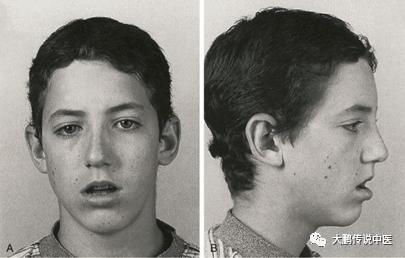

是否因为腺样体肥大,导致慢性口呼吸,从而出现特殊的面容,这个问题存在争议。理论上,口呼吸会导致面部狭长、硬腭高拱、下颌内缩这样的面容,如果是腺样体肥大的导致的,之前会称为「腺样体面容」。

但是现在虽然很多资料也会写「腺样体面容」,但都会加以注明是可能导致或者说还不明确。因为以上说法还没有被完全证实,有的研究认为是这样,有些则不符合;另外多久的口呼吸能导致这个面容也不知道。所以,目前不是说只要有腺样体肥大就会出现特殊面容。

5.腺样体肥大症状明显,并且已经出现特殊面容的孩子,排除了口腔原因,建议进行手术,但是效果不能确定。